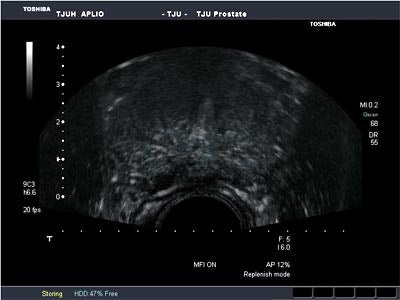

MFI may be of help in this setting. With this flash-replenishment technique, high-power flash pulses destroy the contrast microbubbles while low-power pulses demonstrate replenishment, Halpern said. In a composite image, the vascular architecture is constructed through maximum intensity capture of temporal data in consecutive low-power images, he said.

Sixty patients with an elevated prostate-specific antigen (PSA) level (≥ 4 ng/mL) or an abnormal digital rectal examination were included in the study. All patients received two vials' worth of Definity (Bristol-Myers Squibb Medical Imaging, North Billerica, MA) in 50 mL of saline via intravenous infusion, followed by CHI and MFI imaging. Scanning was performed on an Aplio scanner (Toshiba America Medical Systems, Tustin, CA) with a 6.5-MHz end-fire transrectal transducer.

| Microflow imaging reveals increased definition of vessels in the prostate. Image courtesy of Dr. Ethan Halpern. |

Contrast-enhanced MFI clearly depicts vascular patterns within the prostate, Halpern concluded. No significant difference was seen in the number of patients detected with five targeted cores compared with 10 systematic cores.